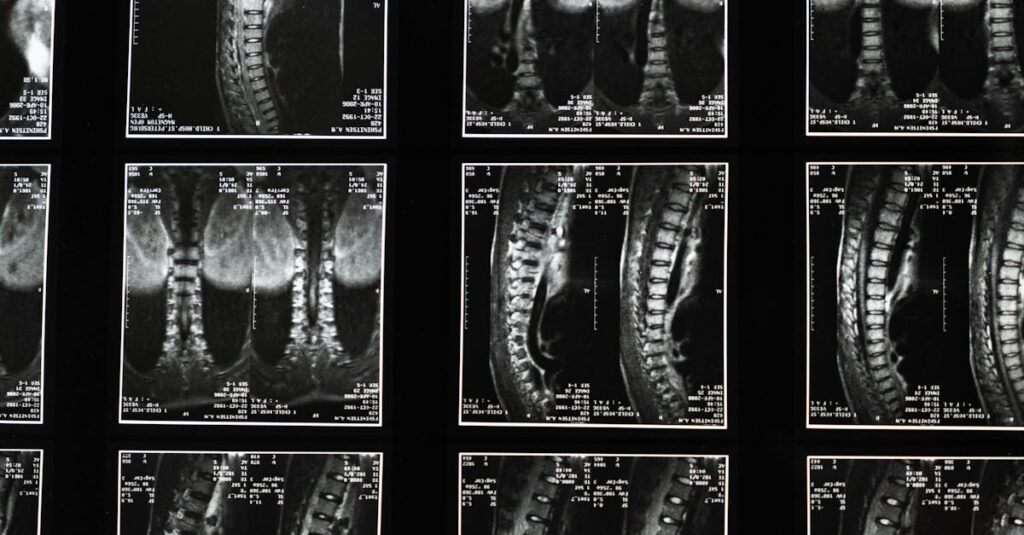

La hernie discale est une affection courante qui touche de nombreuses personnes, causant des douleurs intenses. Elle survient lorsque le noyau gélatineux d’un disque intervertébral fait saillie à travers une déchirure dans l’anneau fibreux. Cette pathologie peut entraîner une pression sur les nerfs voisins, provoquant des douleurs irradiantes, des engourdissements ou une faiblesse musculaire. Afin de traiter cette condition, la décompression spinale est souvent proposée comme une option non invasive efficace.

La décompression spinale est une technique qui vise à soulager la pression sur les disques intervertébraux en créant de l’espace entre les vertèbres. Cela se fait généralement à l’aide d’un appareil de traction qui permet d’étirer doucement la colonne vertébrale. La création de cet espace peut faciliter le mouvement du noyau du disque, aidant ainsi à réduire la douleur et à favoriser la guérison. Cette approche présente plusieurs avantages qui en font un choix privilégié pour le traitement des hernies discales.